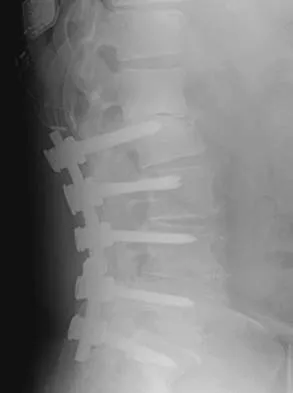

Figures 9a and 9b show the spinal radiographs of a 3-year-old child with short limb dwarfism. The lateral radiograph is obtained with maximal lumbar extension. Management should consist of

The patient has kyphosis in association with achondroplasia. The AP radiograph shows decreased interpedicular distance at the lower lumbar vertebrae, a feature considered to be a distinctive sign of achondroplasia. Most patients with achondroplasia have kyphosis, and this usually resolves spontaneously. When the fixed component is greater than 30 degrees, however, brace treatment is recommended. Spinal fusion is seldom required.